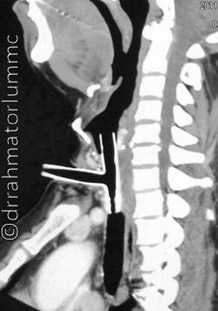

O procedimento consiste em colocar uma órtese na traqueia com um ramo para cima da estenose (em direção à boca) e um abaixo (em direção aos pulmões).

A órtese ou molde traqueal fica sob a estenose e geralmente já é suficiente para mantê-la aberta, assim o paciente volta a respirar pelo nariz e pode falar normalmente.

O procedimento é realizado por broncoscopia rígida, no centro cirúrgico e sob anestesia geral. Inicialmente, pela broncoscopia faz-se uma inspeção da traqueia, reavaliando o grau e extensão da estenose. Após confirmação da necessidade da órtese, este é implantado (colocado) e molda toda extensão da estenose. Pela broncoscopia confirma-se sua posição e o procedimento é encerrado. É muito importante salientar que a técnica varia conforme o modelo de órtese escolhido.